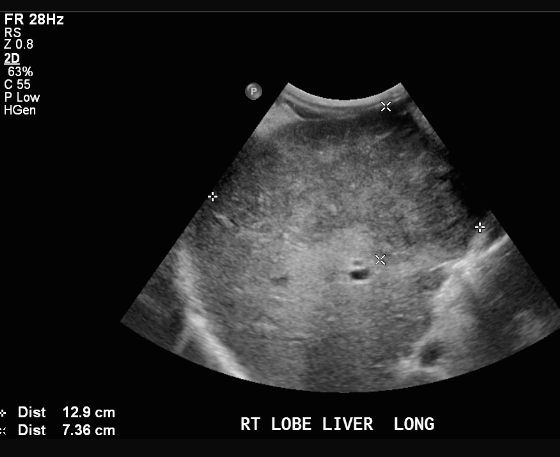

① >5cm hcc sono finding

- massive type

- heterogenous

- irregular margin

- 괴상형, 부정형

- 중심부 응고 괴사진행( cystic change, calcification)